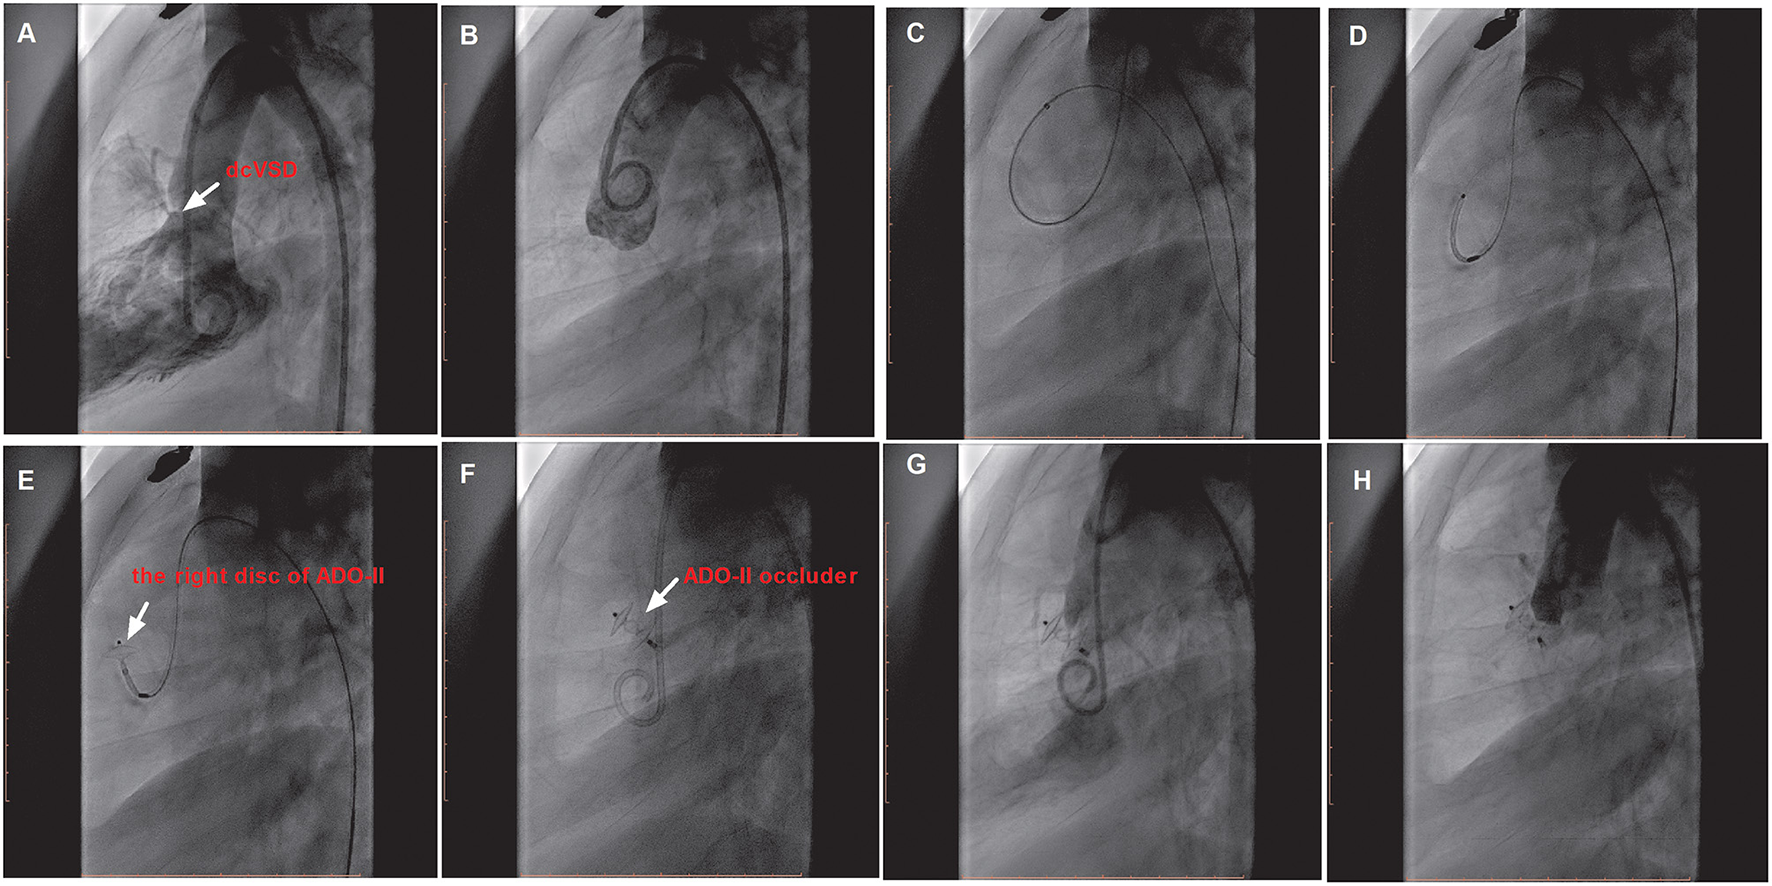

We preferentially attempted the retrograde approach because of the simplified manipulations (Figure 2). A 4 or 5 French cutoff pigtail catheter (SCW Medicath Ltd. Shenzhen, China) was carefully manipulated to pass through the defect into the right ventricle, and a 0.035/0.032-inch guide wire (Terumo, Tokyo, Japan) was advanced into the pulmonary artery or superior vena cava. Subsequently, the delivery sheath (AGA Medical Corporation, MN, USA) was replaced into the right ventricle. The selected device was retrogradely introduced through the delivery sheath. The right disk was pushed out of the sheath and then the delivery system was pulled back gently, finally releasing the waist and left disk until the waist and left disk were confirmed to be located on the left side of the septum. If the control angiography by hand from the sidearm of the delivery sheath and TTE showed satisfactory results without a residual shunt (RS) and new-onset AR, then the device was released.

Figure 2

The procedure of transfemoral occlusion of the dcVSD using the ADO-II device via the retrograde approach. (A) Confirms the location of the deVSD (arrow) by left ventriculography before device closure of it, and (B) Demonstrates the finding of aortography without AR before the procedure. (C–F) Show the processes of the transcatheter technique. (G) Shows the operational success and no RS by left ventriculography, and (H) Shows no AR after device implantation by aortography. dcVSD, doubly committed subarterial ventricular septal defect; AR, aortic regurgitation; RS, residual shunt.